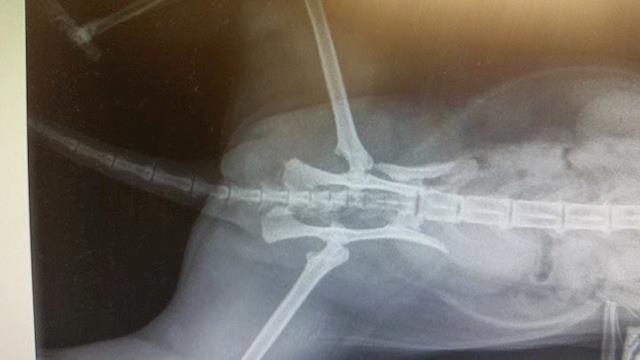

They set her fracture, and it seems it was her left pelvis, I had thought it was the right. So she wasn't lying on the broken side at the vet's the other day; she was lying on the not-broken side.

This evening, first working day of the week (Monday was Queen's Birthday weekend) I saw the surgeon. His name is David, and he put the x-rays up on screen again, and took me through the process of what would be done. She will have something called a 'string of pearls' which I visualise as a meccano piece with lots and lots of bolts. The bolts go into the bone, I guess they must be self-tapping. They hold the two slivers together.

He explained that so many days after the event (it will be nearly a week on Wednesday) all her muscles will have tightened and it will be very difficult to get the pelvis back to where it belongs; but he should at least be able to make a good job of widening the pelvis enough for faeces to go through it. See the x-ray attached, for what has happened. The pelvis has snapped off and shunted up forwards into the actual pelvis area.